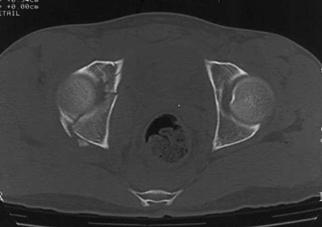

Compresie laterala

Fracturi pelviene multiple Fracturi pelviene multiple

Compresie bilaterala Compresie bilateralaAspect CT

Fracturi pelviene multiple Fracturi bilaterale de ramuri pubiene

Compresie bilaterala Aspect CT Disjunctie sacro-iliaca stanga Compresie antero-posterioara